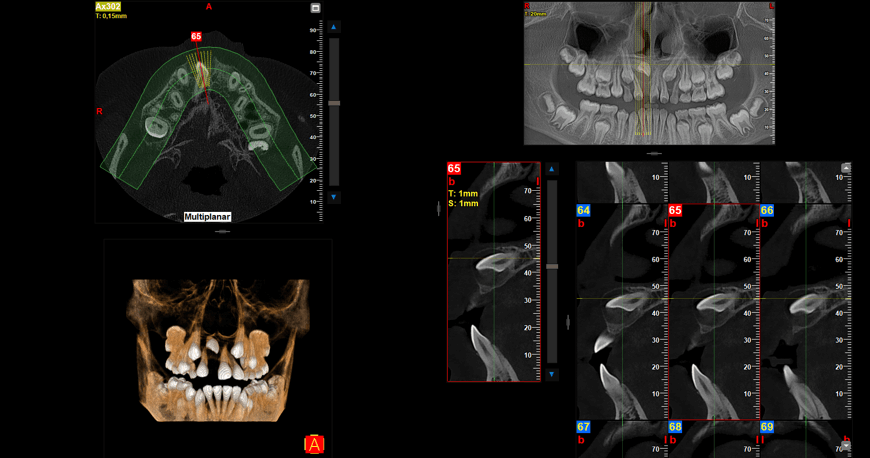

Para diagnóstico radiológico se utiliza CBCT bimaxilar FOV 10 x 8 realizada previo a la colocación de aparatología fija, en donde se observa al diente 1.1 retenido en el piso de fosas nasales en posición horizontal con su saco pericoronario desprovisto de recubrimiento óseo en el borde incisal. (Fig 5)

Fig 5. Cortes en ventana MPR y renderizado 3D

El ápice del diente 1.1 está ubicado en el centro del paladar duro en sentido sagital por lo que el riesgo de necrosis pulpar posterior a la tracción ortodóntica es una complicación a tomar en cuenta en el presente caso. (Fig 6)

Fig 6. Reconstrucción PANOREX y cortes sagitales

La paciente se encuentra en etapa de recambio dentario, se observan los dientes 1.3 y 2.3 en etapa de evolución intraósea, dientes deciduos 5.3 y 6.3 con la reabsorción fisiológica simétrica propia de la edad. Se confirma que la edad cronológica de la paciente coincide con la etapa eruptiva de la misma. (Fig 7 y 8)

Fig 7. Renderizado 3D frontal - Fig 8. Renderizado 3D vista superior